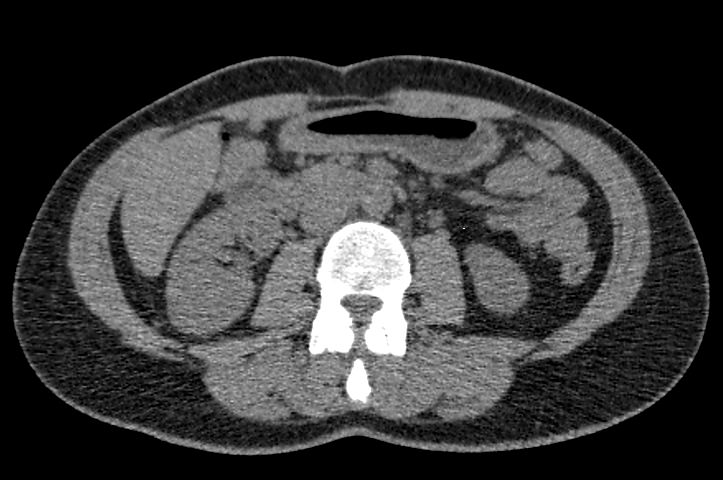

Методика КТ позволяет оценить анатомическое строение почек, надпочечников, состояние мочеточников и мочевого пузыря, кроме того, дает возможность визуализировать сосудистую систему и регионарные лимфатические узлы.

Сканирование применяется для выявления воспалительных заболеваний почек, чашечно-лоханочной системы, мочеточников и мочевого пузыря, также позволяет обнаружить конкременты на фоне мочекаменной болезни, диагностировать доброкачественные и злокачественные новообразования, точно классифицировать кистозные образования по системе Bosniak, что особенно важно для урологов и нефрологов, а также определить степень поражения регионарных лимфатических узлов. Кроме того, КТ используется для диагностики травматических повреждений органов мочевыделения, аномалий развития почечно-лоханочной системы, дает максимальную информацию для хирурга при планировании оперативного вмешательства.

Что показывает КТ почек, мочеточников, мочевого пузыря

- опущение почек;

- аномалии развития почек, мочетоников

- доброкачественные и злокачественные новообразования;

- камни (конкременты);

- уретероцеле

- сосудистую патологию (сосудисто-мочеточниковый конфликт, инфаркт почки);

- последствия оперативных вмешательств;

- увеличение лимфоузлов в брюшной полости, забрюшинном пространстве и малом тазу;

- травматические изменения

- патологии сосудов малого таза.